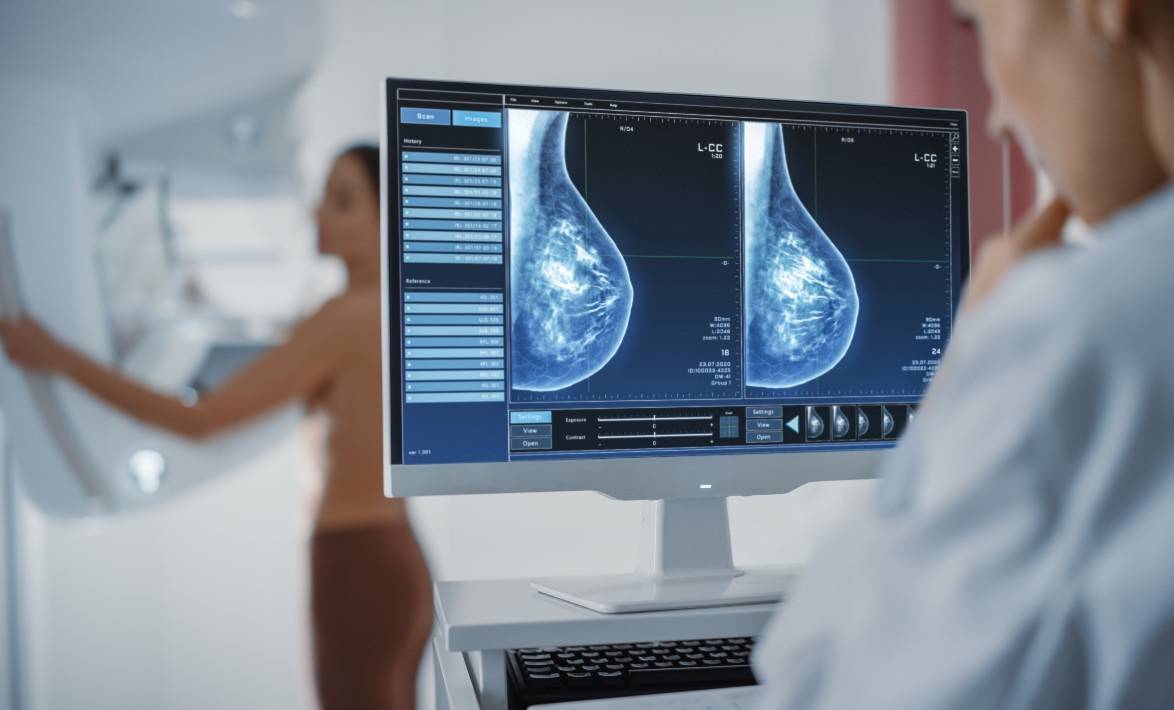

Un artículo publicado por un equipo del Instituto de Salud Carlos III sugiere que la densidad mamográfica puede asociarse con los subtipos de cáncer de mama, y relacionarse con el desarrollo de tumores HER2+ o triple negativo, que tienen peor pronóstico.

Un estudio realizado desde el instituto de Salud Carlos III (ISCIII) ha analizado la relación entre densidad mamográfica y los subtipos de cáncer de mama, y sus resultados sugieren que una alta densidad mamográfica podría estar asociada con el desarrollo de tumores con peor pronóstico.

El estudio, publicado en la revista Breast Cancer Research, ha evaluado a 714 pacientes diagnosticadas entre 2014 y 2019 en ocho hospitales de cuatro comunidades autónomas españolas. Los resultados sugieren que una mayor densidad mamográfica podría estar asociada con el desarrollo de tipos tumorales más agresivos, como los HER2+ y los triple negativo, que tienen peor pronóstico.

Los autores y autoras de este trabajo, liderados por la investigadora del CNE Virginia Lope, explican que la densidad mamográfica, que refleja la proporción de tejido fibroglandular frente al tejido graso en una mamografía, constituye un importante factor de riesgo de cáncer de mama, y podría influir de manera diferente en el desarrollo de estos subtipos. En la investigación también se ha estudiado la posible influencia del índice de masa corporal y el estado menopáusico.

Para el desarrollo del estudio, se recogió información epidemiológica, clínica y de anatomía patológica mediante cuestionarios a las participantes y revisión de historias clínicas. El 69 % de las participantes presentó tumores HR+, un 19 % el subtipo HER2+ y un 12% el triple negativo.

La densidad mamográfica media fue del 26 %. Las mujeres con densidad mamográfica superior al 50 % presentaron un menor porcentaje de tumores con mejor pronóstico (HR+), mientras que el porcentaje de tumores HER2+ y triple negativo -los más agresivos- fue un 36 % y un 23 % mayor, respectivamente, en comparación con las mujeres del grupo de menor densidad.

Virginia Lope explica que estos patrones se observaron principalmente en mujeres pre/perimenopáusicas y en aquellas con sobrepeso u obesidad: “Aunque los hallazgos son preliminares y requieren confirmación, apuntan a que la densidad mamográfica alta podría ser un marcador relevante para identificar a mujeres con mayor riesgo de desarrollar formas más agresivas de cáncer de mama”, concluye.